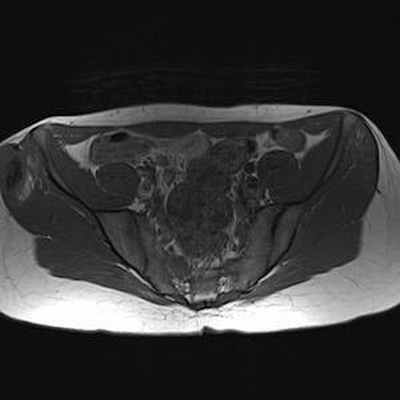

МРТ: чётко видимая хрящевая шапочка, имеющая геперинтенсивный сигнал на T2 (DP)-ВИ и изоинтенсивный сигнал на Т1-ВИ, неправильной формы и очень плотная (23 мм), принимающая дольчатый вид, вызывающая подозрение на саркоматозную дегенерацию. Периферическое повышение сигнала после инъекции.

IRM Abdomen Axial Pondération T1

IRM Pelvis Axial Pondération DP